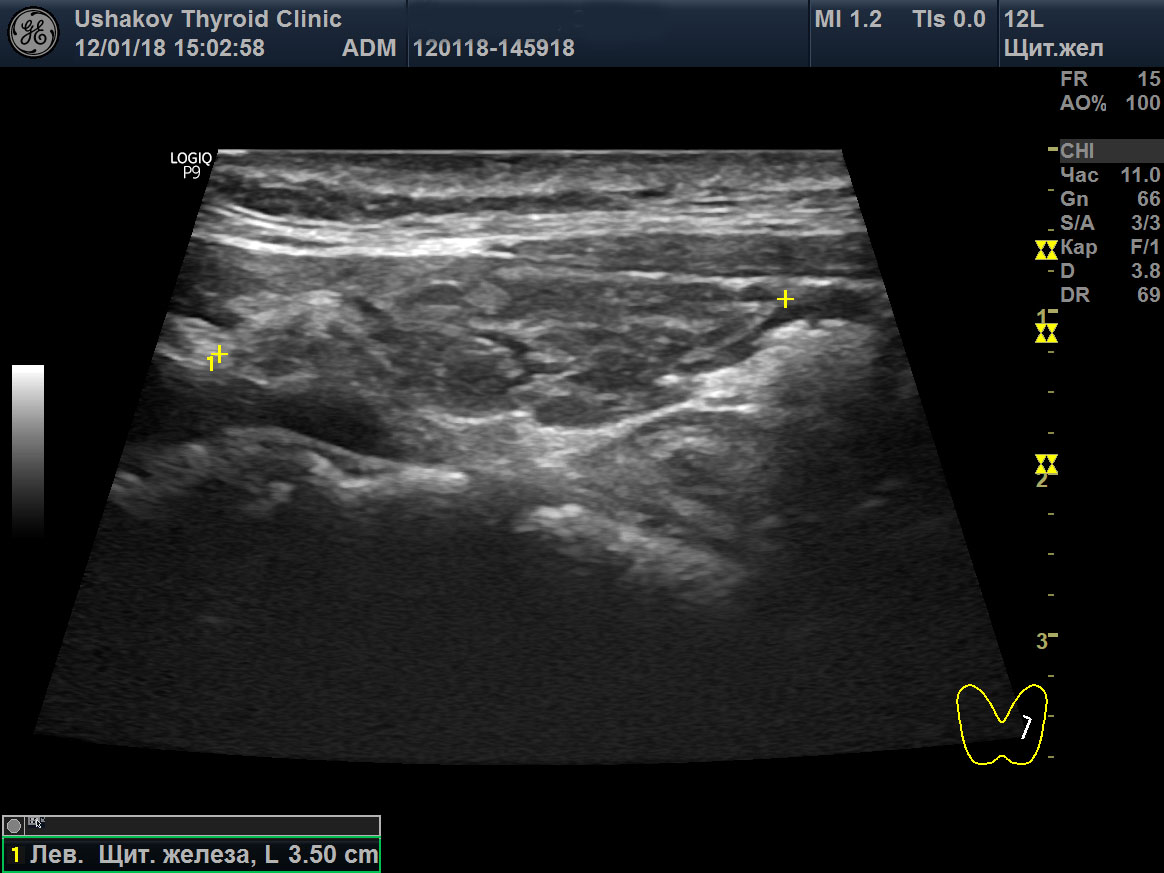

Увеличение левой доли щитовидной

Увеличение левой доли щитовидной 112 фото